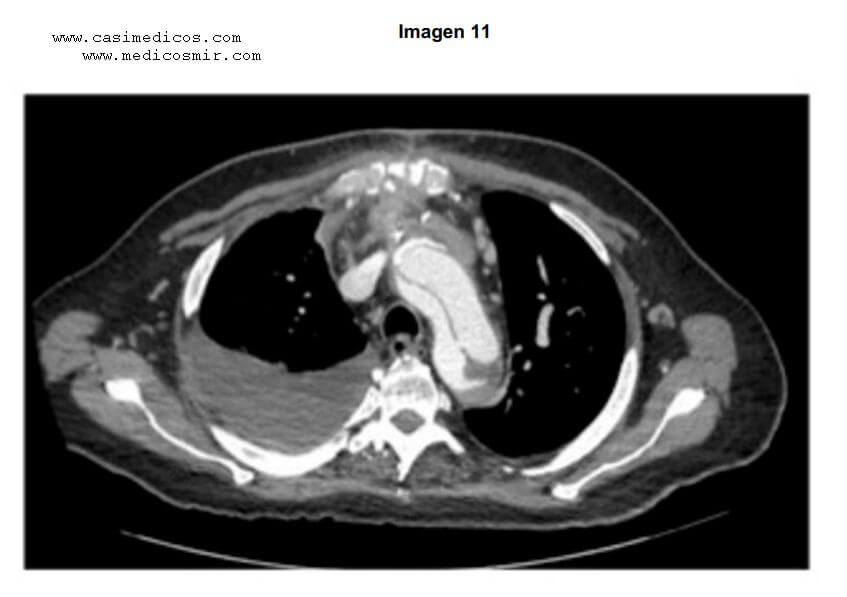

Pregunta 11.

Pregunta asociada a la imagen 11.

Hombre de 52 años que consulta por dolor centrotorácico desgarrador de 30 minutos de duración. A la exploración está inquieto y

sudoroso. La tensión arterial es de 190/110 mmHg en ambos brazos. A la auscultación no hay soplos cardiacos ni estertores crepitantes. El

electrocardiograma está en ritmo sinusal a 90 latidos por minuto sin alteraciones de la repolarización. En la angioTC torácica se observa

la imagen que se adjunta. ¿Cuál es el diagnóstico más probable?:

- Hematoma intramural.

- Úlcera penetrante arteriosclerótica.

- Pseudoaneurisma de aorta.

- Disección de aorta tipo A de Stanford.

AngioTC torácica en que muestra un flap intimal en la aorta torácica que corresponde a una disección de aorta tipo A de Stanford. RESPUESTA 4.